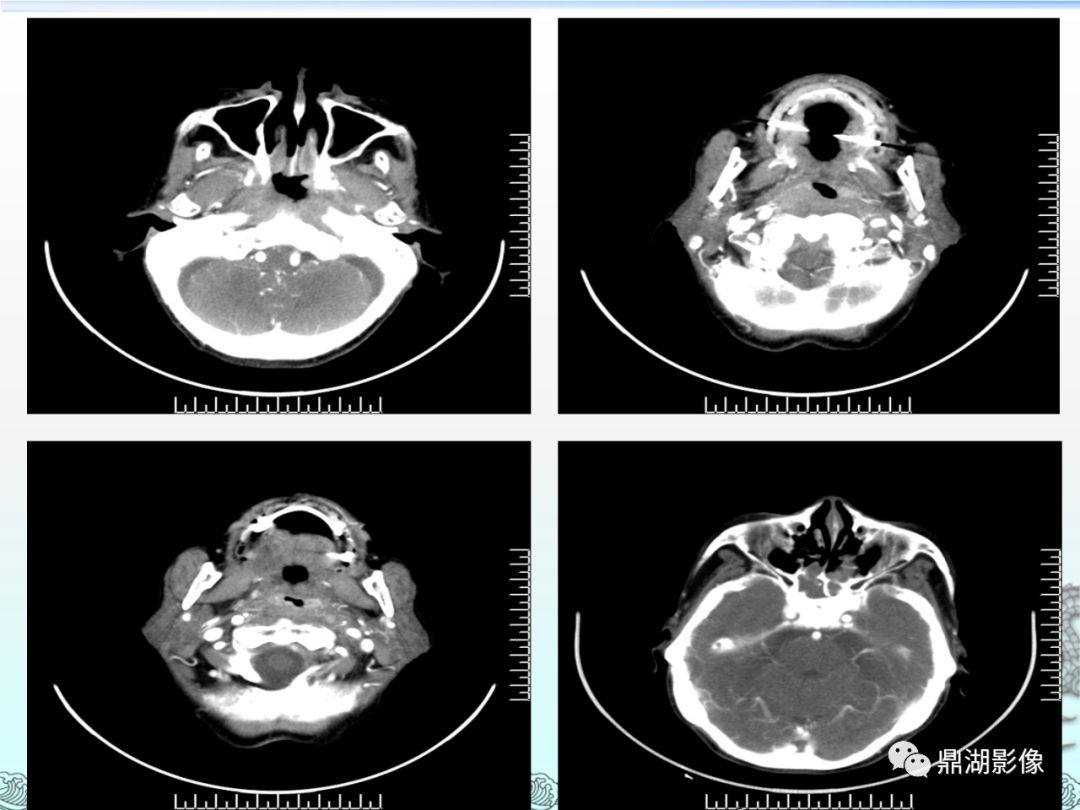

团队收治的一位难治性鼻窦癌患者ini-1缺失,罕见分类,团队开启烧脑

ct也提示有鼻咽部肿物,eb病毒抗体呈阳性,这些都是鼻咽癌的危险指标

鼻咽癌的ct诊断与鉴别诊断整理